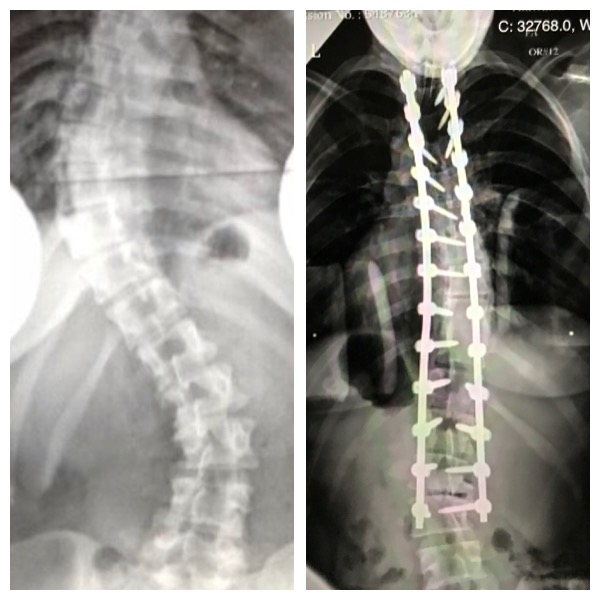

Scoliosis has always been a part of my life. At age 5, I started wearing a brace through lower and middle school. The big, old, bulky plaster ones that were so embarrassing, limiting, and uncomfortable, especially as a young kid. After years and years of being a competitive swimmer through college and building up my core, my scoliosis pain subsided and the curves improved a bit. It wasn't very noticeable, except for the aesthetics of how I looked (with a constant lean to one side and was obviously over developed on one side of my back). In 2015, about 8 years post-college/post-swimming, the pain came back and the degrees of my curves worsened. I initially saw Dr. Kim for a consultation but I wasn't ready to pull the trigger on surgery. Fast forward to 2017 (10 years post college/post swimming) and I knew I couldn't live my life like this - my posture was getting worse, I was self-conscious about how my back looked, and I couldn't stand, walk, sleep, or sneeze without being in pain. I saw Dr. Kim again and knew I was ready to make the change for the better. In Spring 2017, I had a spinal fusion from my T3-L3 and I have never looked back (no pun intended)! This past Spring 2019 I got married with my scar proudly on display in the type of dress that had a back I would have never dreamed of wearing before. I can walk, ski, golf, workout, run, sleep, and live my life pain-free. I am in constant awe of and have deep gratitude for Dr. Kim and his team at HSS for being the absolute best there is. They are a flawless group of professionals who are kind, patient, confident, and honest- not to mention the most talented individuals you can possibly find. I still look forward to my follow up appointments years later to visit HSS and Dr. Kim. Thank you for all you have done for me!